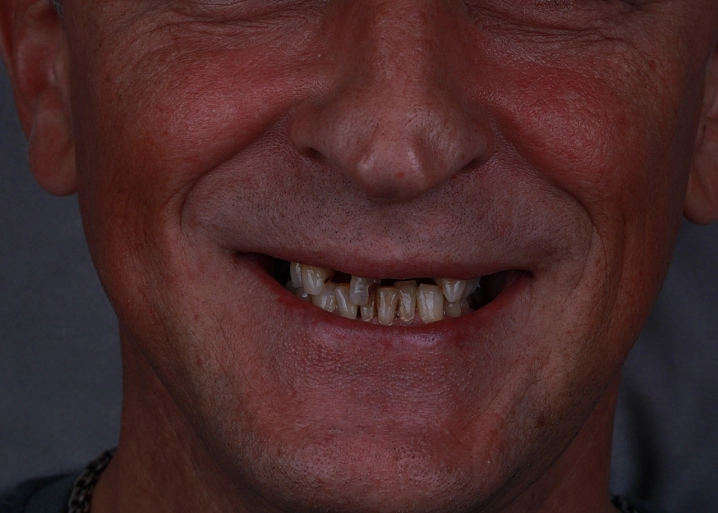

Проведена полная эстетическая реставрация зубных рядов верхней и нижней челюстей винирами E-max. Восстановлена форма, размер, цвет и поверхность фронтальных зубов, достигнута гармоничная улыбка.